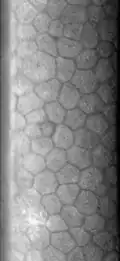

Эндотелий роговицы, задний эпителий роговицы — монослой специализированных плоских клеток, выстилающих заднюю поверхность роговицы и входящих в соприкосновение с содержимым передней камеры глаза. Гексагональные клетки эндотелия содержат повышенное количество митохондрий и осуществляют транспорт жидкости и растворенных веществ, поддерживая роговицу в слабо дегидрированном состоянии, необходимом для её прозрачности. Площадь клеток примерно одинакова; при значительном разбросе их размера говорят о наличии полимегетизма.